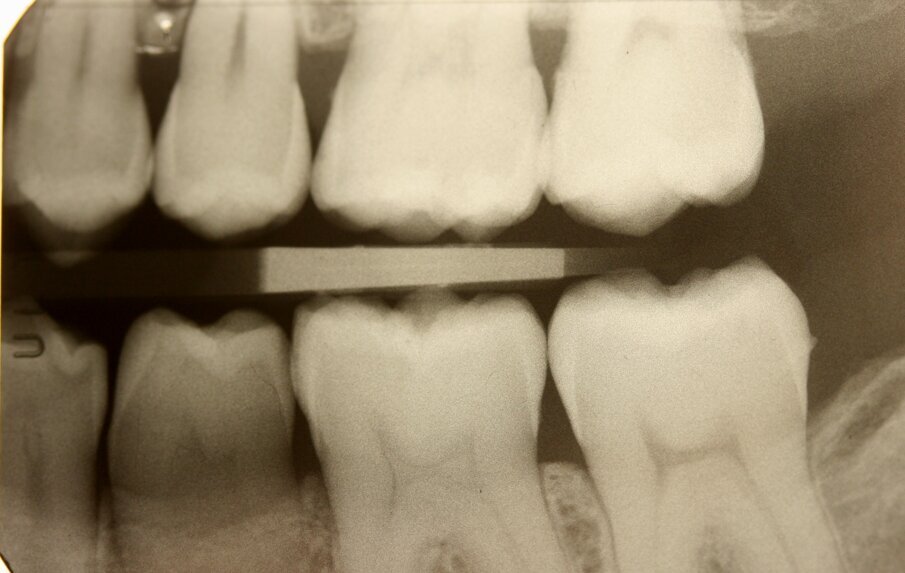

La paziente, FF di anni 38, è giunta alla mia osservazione per la cura delle lesioni cariose presenti. All’esame obiettivo non erano evidenti lesioni cariose di notevole entità (Figg. 1, 2): solo attraverso le bite-wing (Figg. 3, 4), mezzo indispensabile per la diagnosi odontoiatrica in conservativa, si evince la presenza di numerose lesioni cariose coinvolgenti il tessuto dentinale. La paziente richiedeva il raggiungimento di un risultato estetico ottimale, ovvero la mimetizzazione del materiale composito con il tessuto smalteo; oltre a questa esigenza si doveva unire quella di effettuare una riabilitazione funzionale ovvero, trattandosi del settore posteriore, che sopportasse il carico masticatorio garantendo la minima usura possibile nel tempo. Alla paziente è stato proposto un piano di trattamento che prevedeva la cura diretta delle lesioni cariose suddivise per quadranti e la riabilitazione indiretta dell’elemento 47 in modo da permettere la migliore precisione marginale garantendo un ottimo follow-up a lungo termine. Si è proceduto con la riabilitazione mediante il composito di recente introduzione Enamel Plus HRi Bio Function (Micerium, Avegno, Genova). Bio Function è disponibile in 3 smalti: BF1 basso valore - BF2 medio valore - BF3 alto valore e in 9 dentine: BD0 - BD0,5 (per restauri di denti particolarmente bianchi o sbiancati) BD1 (A1 Scala Vita) - BD2 (A2 Scala Vita) - BD3 (A3 Scala Vita) - BD3,5 (A3,5 Scala Vita) - BD4 (A4 Scala Vita) BD5 - BD6.

Fig. 3_Bite-wing di destra.

Fig. 4_Bite-wing di sinistra.